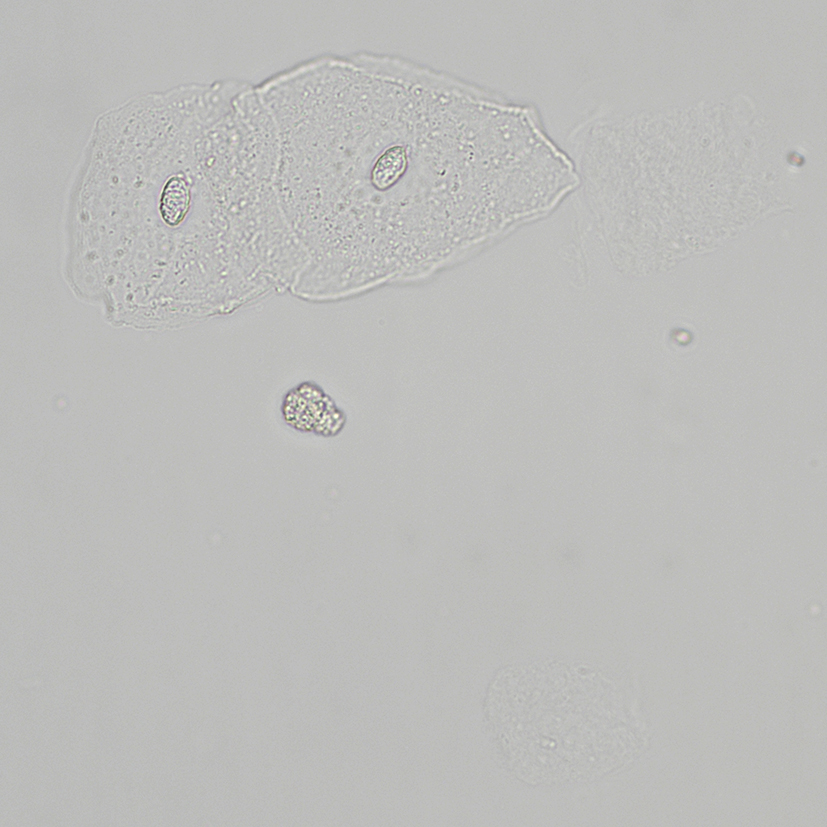

MQ 2024-4 U4 Urinsedimente